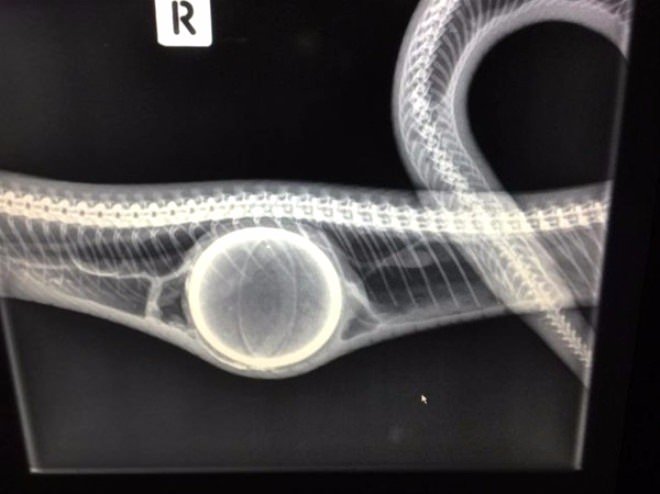

Yuttuğu cisim yüzünden hareket dahi edemeyen yılanı kurtarma operasyonu anbean kameraya çekildi.

Avustralya'da bir kadın ve arkadaşı, bahçede gördükleri yılanın midesinde ki koca şişliği anlamlandıramadı ve onu kusturmak için yaklaşık 20 dakika boyunca masaj yaptılar.

Sonunda tenis topunu çıkararak yılanı kurtarmayı başaran kadının yılanı kurtarma çabaları cep telefonu ile kaydedilen görüntülere yansıdı.